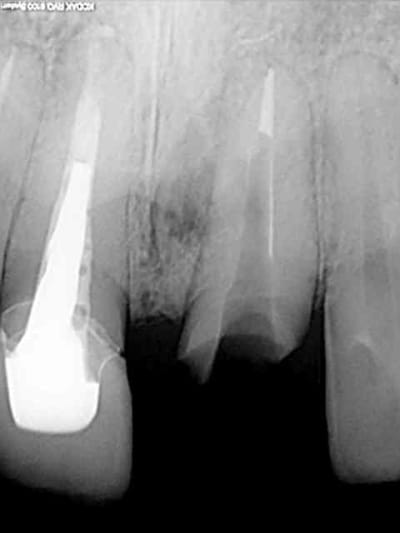

voici encore un autre cas avec du PX encore tout chaud de ce matin...

homme 35 ans veut faire recoller sa couronne 21.

le tenon est tordu, je refais une provisoire mais à la radio je lui dis que j'ai un doute quant à la survie de la dent parce qu'il y a une image pas très nette en mesial de la racine.

je l'envoi faire quelques coupes tomo (vivement que j'ai cone beam! )

le resultat est édifiant et sans appel; la racine est à extraire!

1 radio départ

1 radio départ

2-3-4 cas initiale avec provisoire

5 extraction avec periotome

6-7 l'objet du délit...

8 forage

9 jauge de profondeur

10 l'AXIOM PX

(diamètre 4; dans le cas précédent c'était un diamètre 3.4 on voit qu'ici il y a une réduction du diamètre du col de l'implant contrairement au 3.4 pour eviter de fragiliser l'implant)

voili-voilà :

avant d'envoyer le patient passer son cone-beam je n'étais pas convaincu que il y avait un kyste. comme quoi!